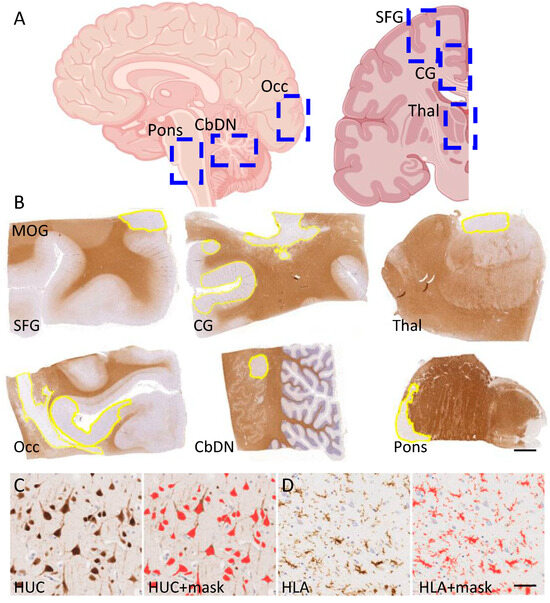

2.4. Digital Pathology and the Quantification of Demyelination, Inflammation and Neuron Density